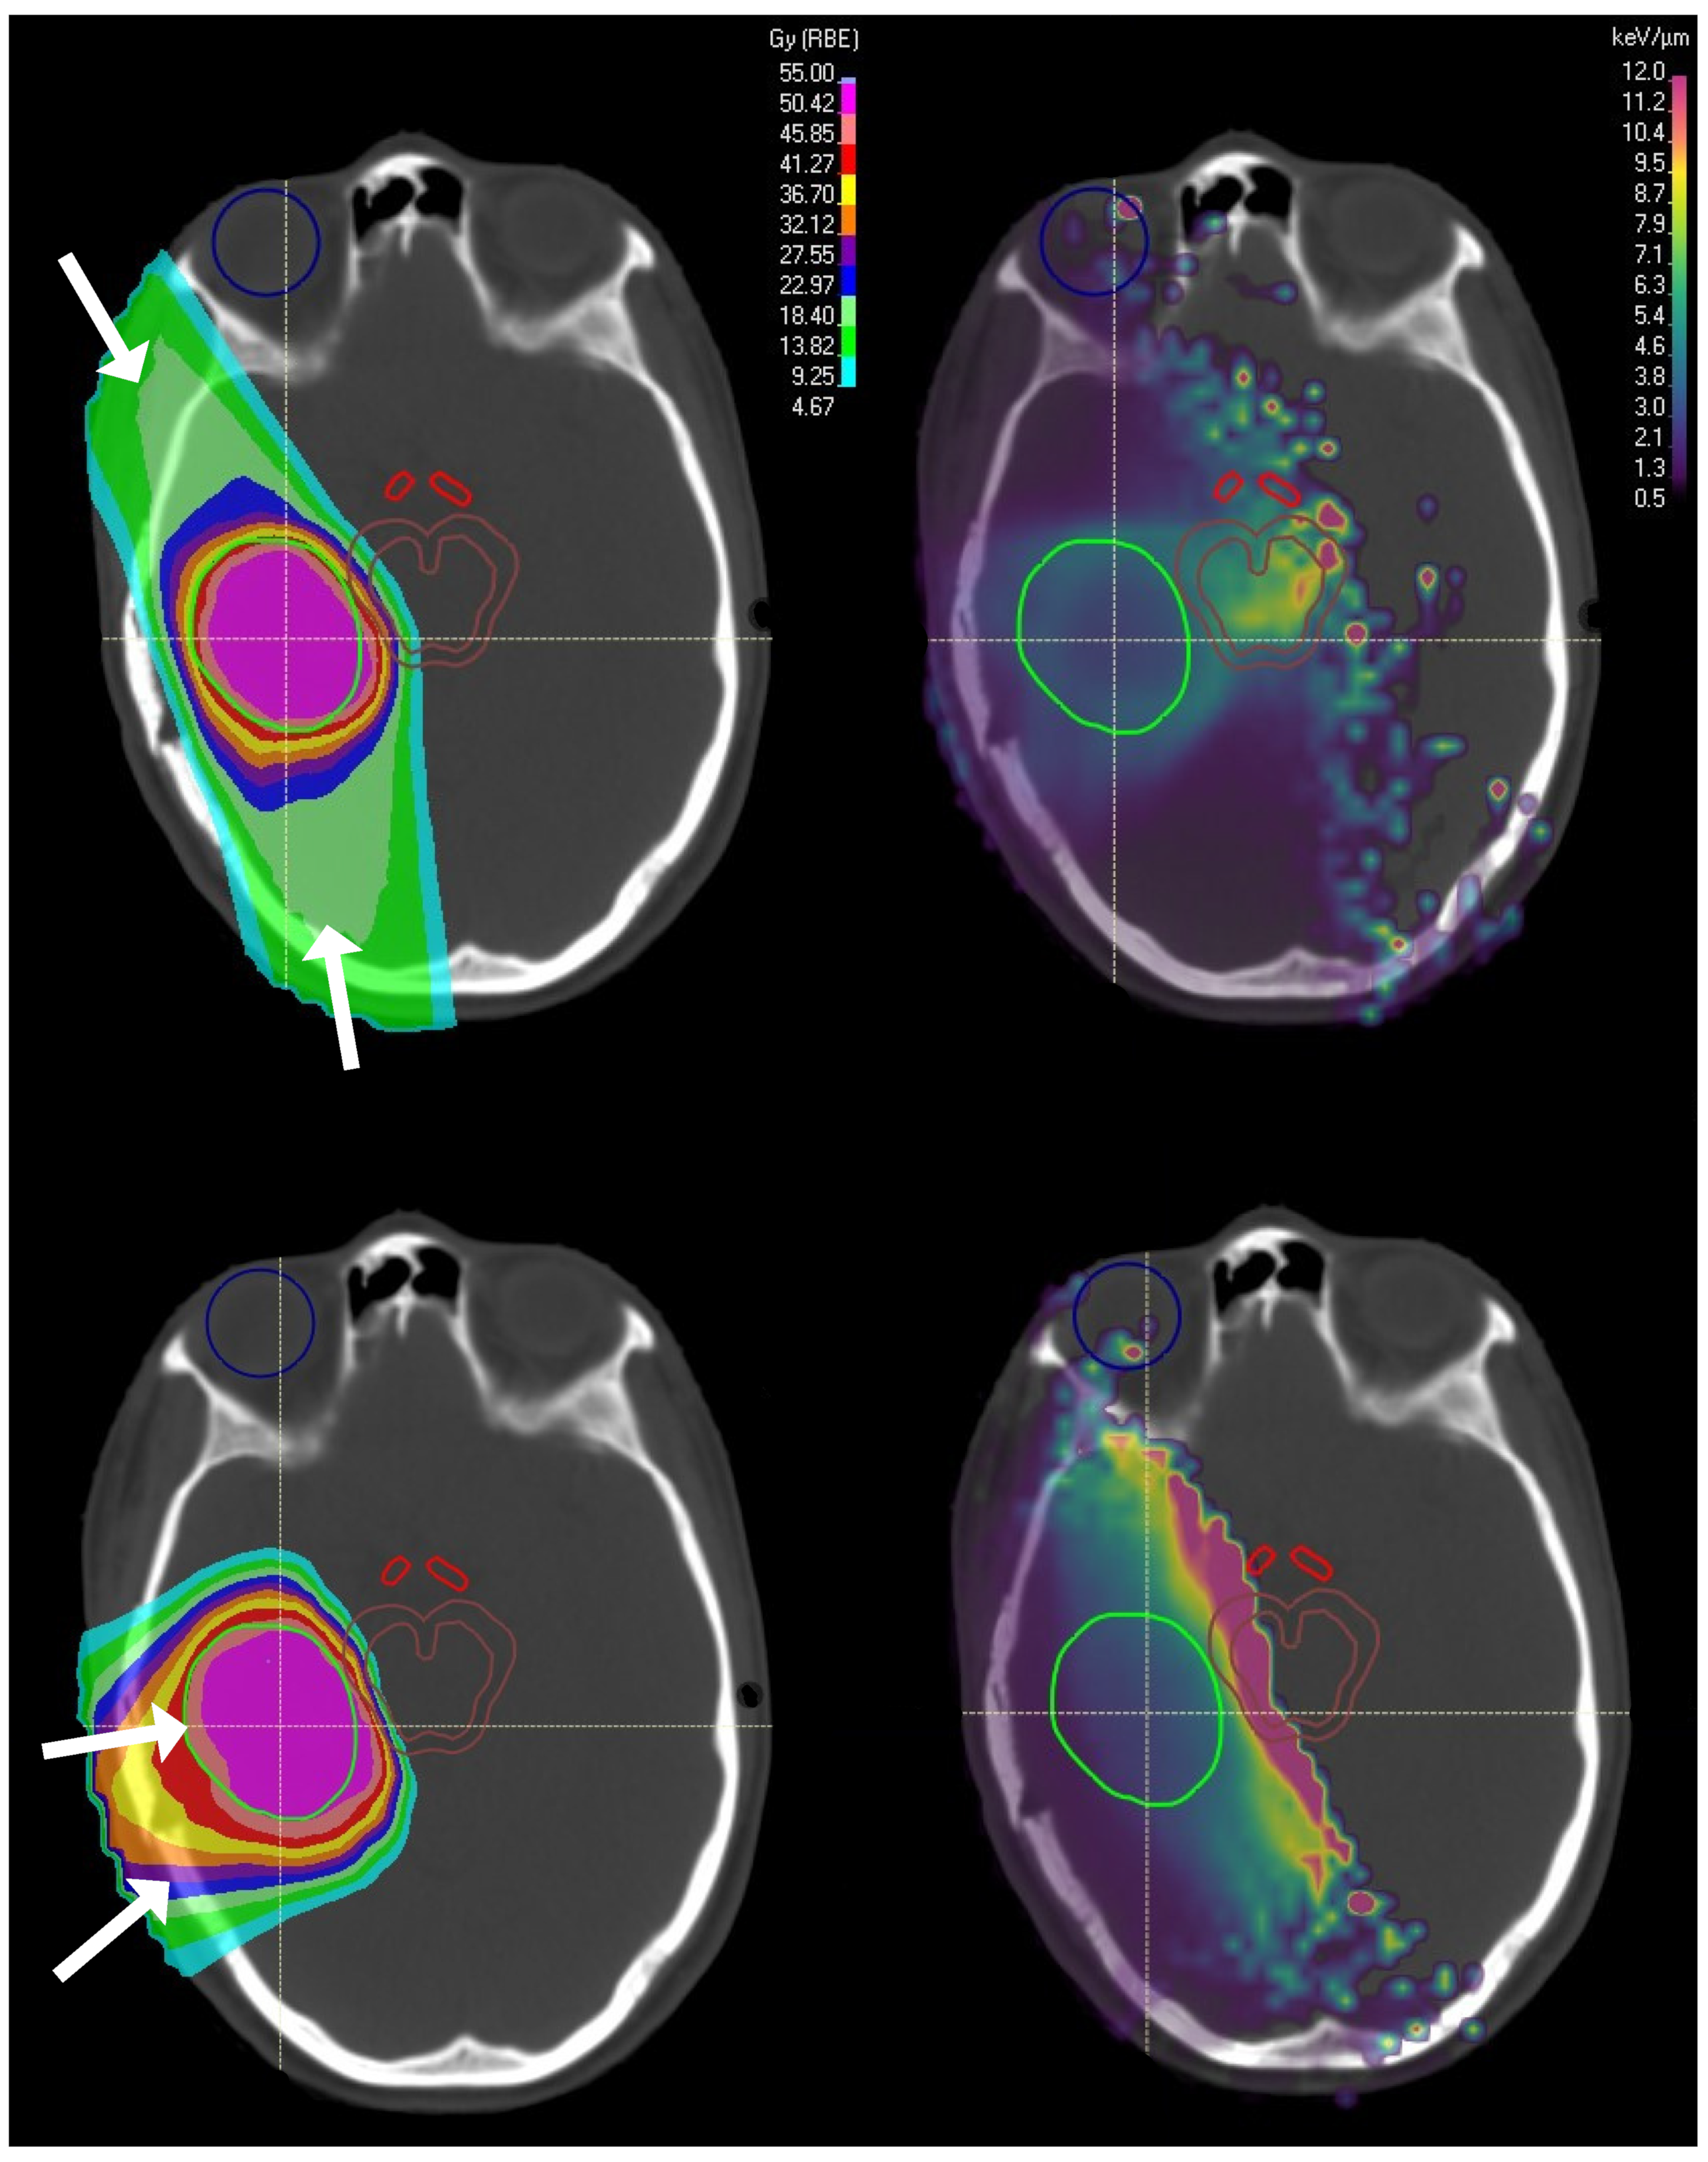

Oden et al. [17] ![]()  | 3 Intracranial | PBS, 50.4–54 GyRBE (28–30 FX), 2 opposed beams | Brain toxicity, Blindness | 5–10 (toxicity), 9 (blindness) | Elevated LET of 4–6 keV/m with high dose occurred inside toxicity volumes. |